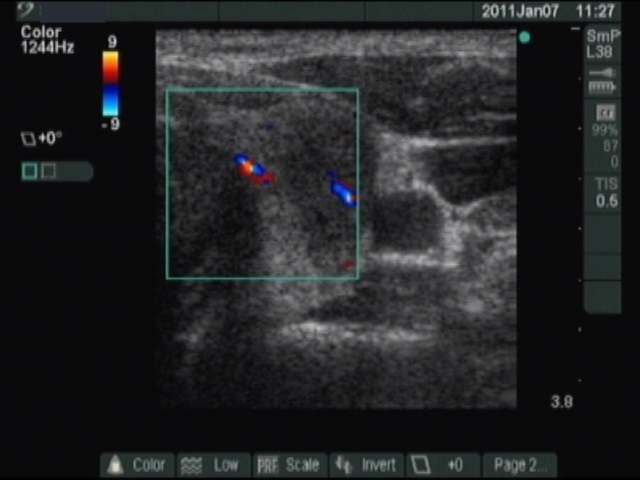

Ultrasonography: there were a hyperechogenic and a moderately hypoechogenic nodule in the enlarged right thyroid, while a hypoechogenic lesion with blurred borders in the left lobe. The vascularization was not specific. (The picture demonstrate the left thyroid.)